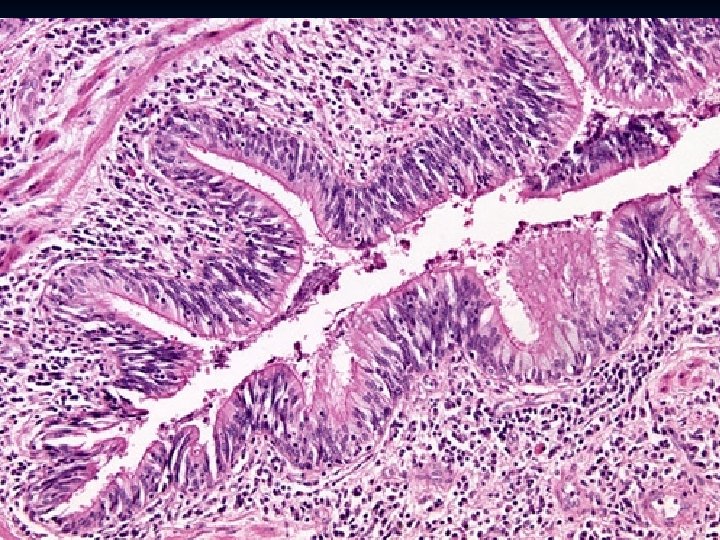

n Histology: -Thick basement membrane -Edema and infiltration of the bronchial walls by inflammatory cells with prominence eosinophils, - Hypertrophy of bronchial wall muscle. of